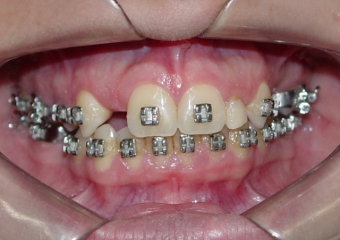

Próteses de porcelana sobre implantes

Sorriso final do caso terminado em maio de 2012